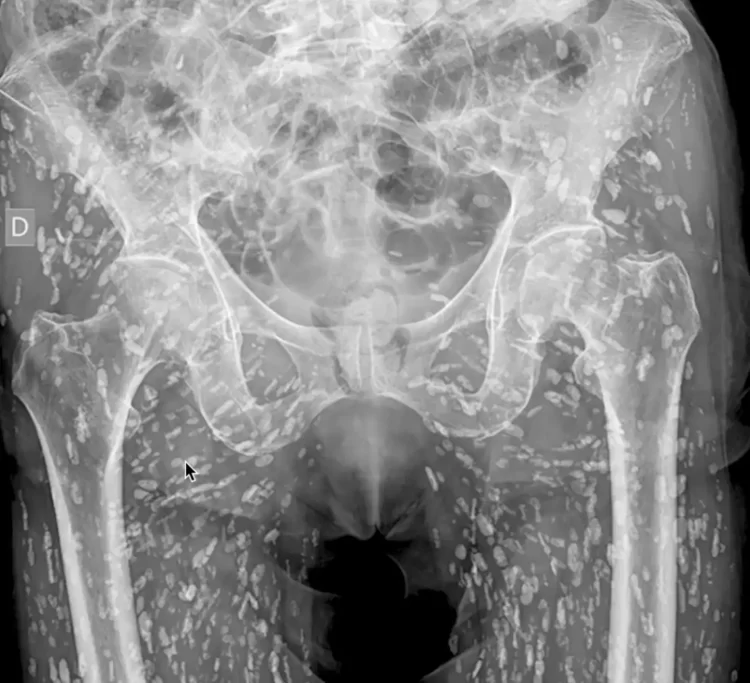

Doctor Shares Shocking X-Ray of Person Infested with Calcified Tapeworm Eggs

An ER doctor recently shared “one of the most insane X-rays he has ever seen,” showing a person’s lower body infested with hundreds of calcified tapeworm eggs. Tapeworms are parasites that usually anchor themselves to the inside of the intestines of their host, absorbing nutrients directly from the gut, but few people know that tapeworm […]